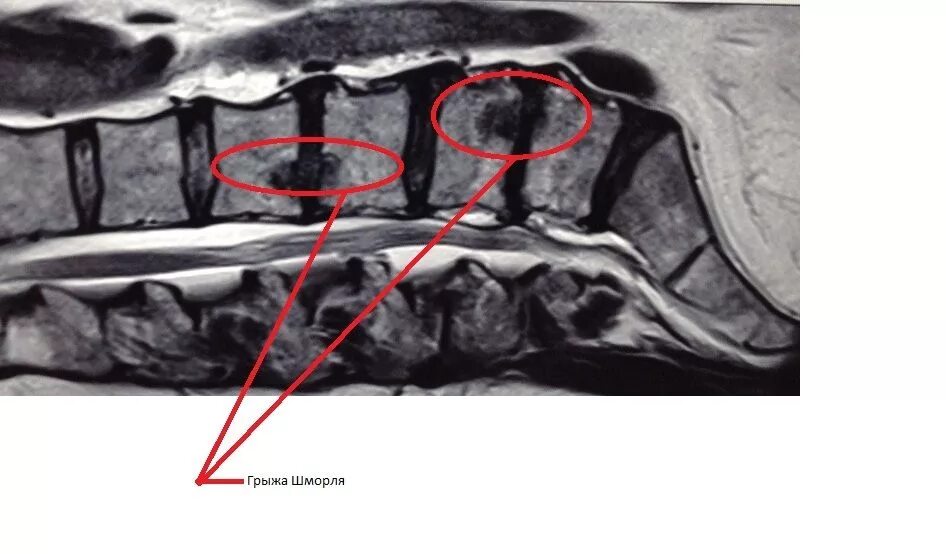

Грыжа шморля протрузия